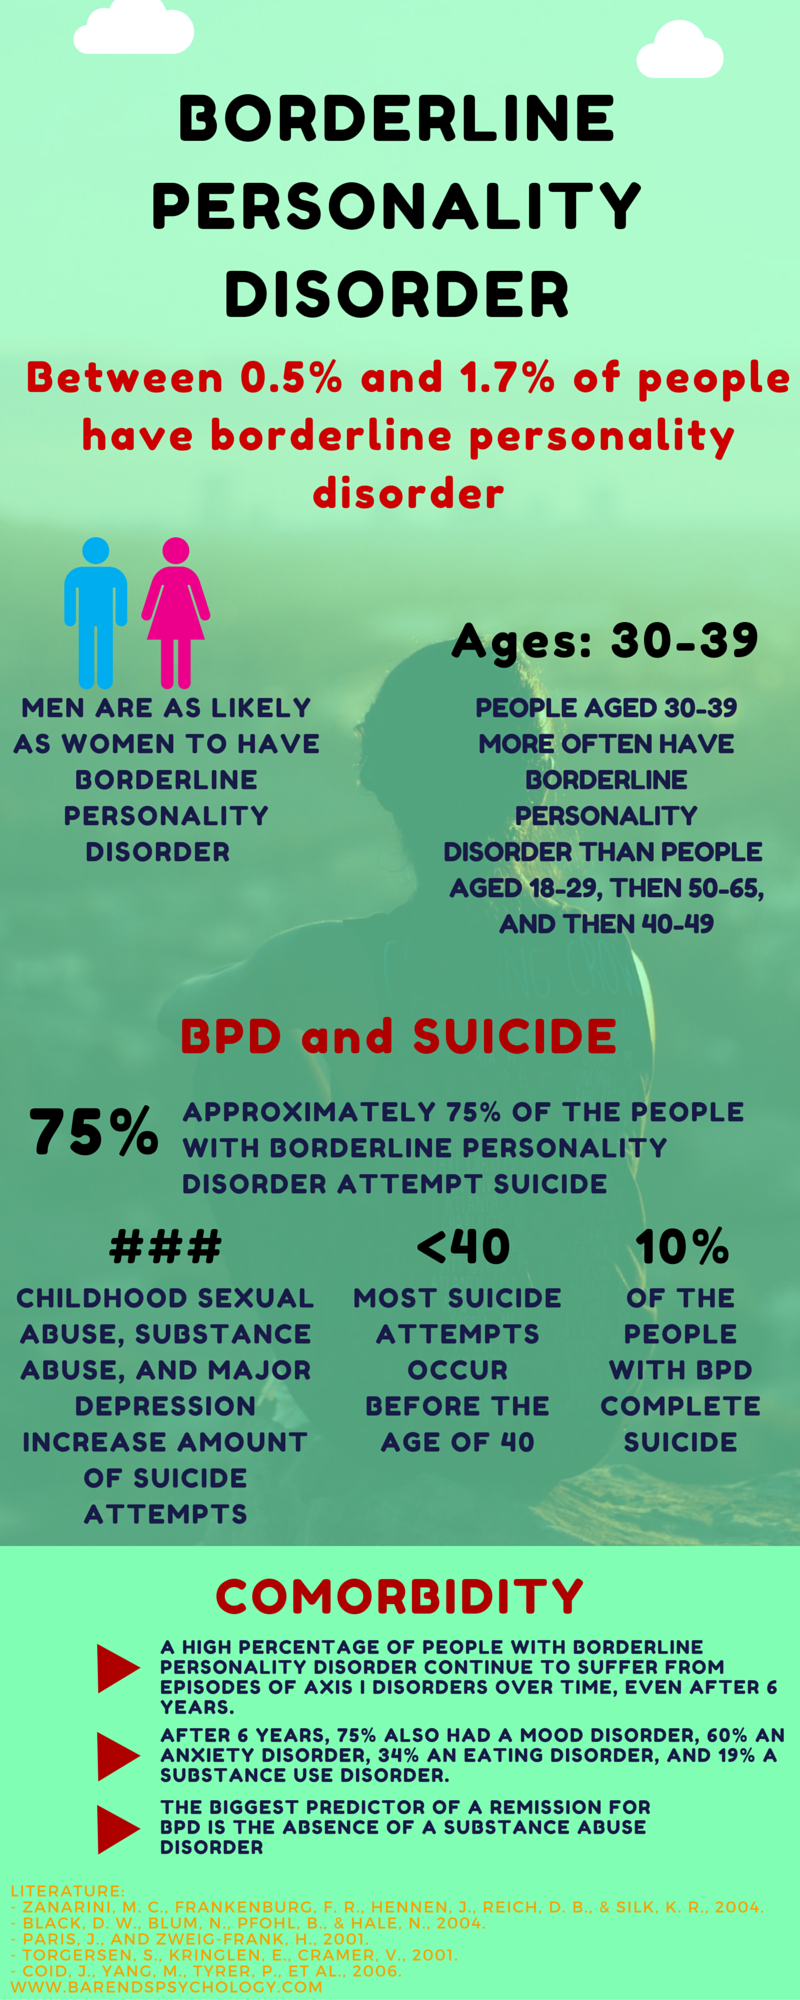

Borderline personality disorder: symptoms and characteristics.